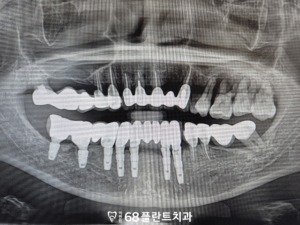

◆ 전 > 후 ◆

치료 마무리 후 환자분께서는

잇몸뼈가 녹아 치아가 흔들리고

그렇다보니 한쪽으로만 식사를 하게 되어서

불편했는데 지금은 양쪽으로 편하게

식사를 할 수 있어 매우 만족하셨습니다.